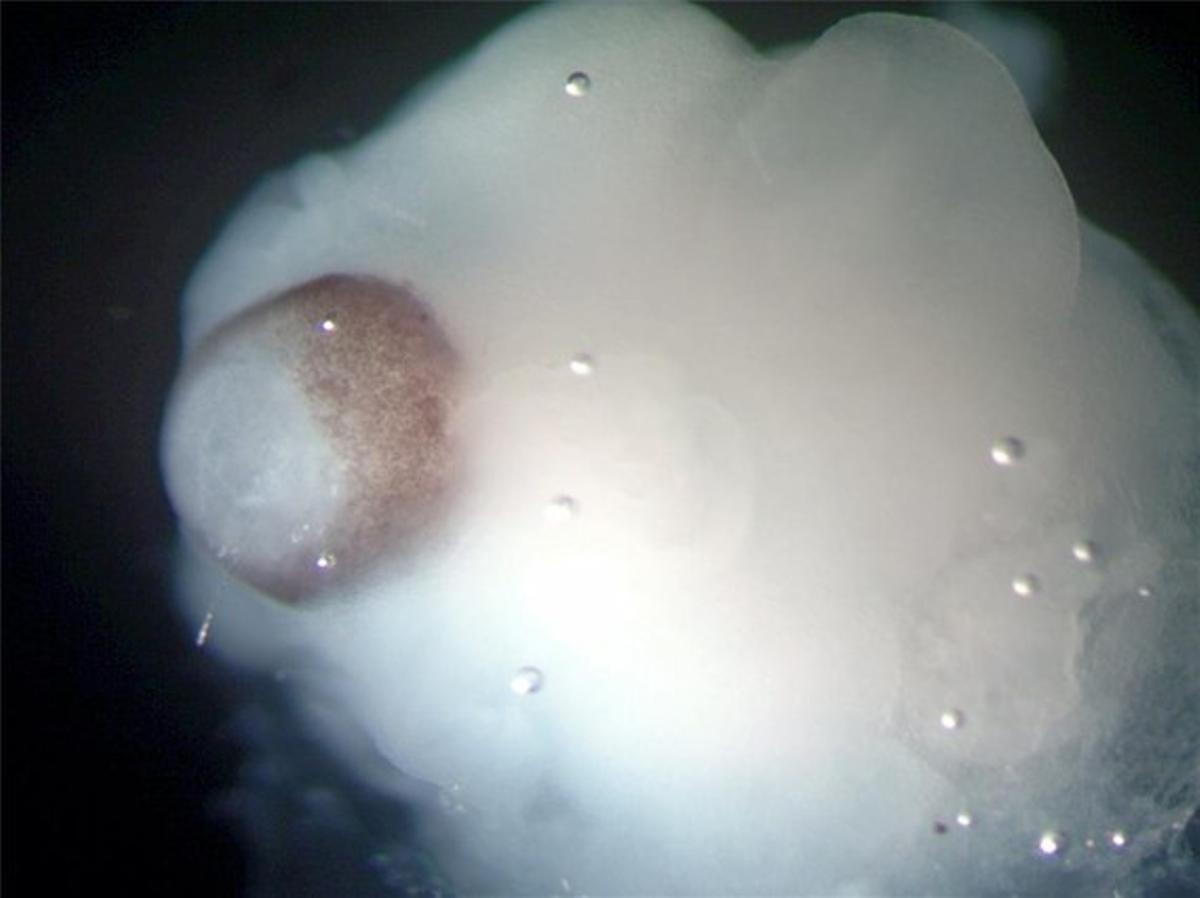

Imagen de uno de los cerebros en desarrollo creados a partir de células madre / periodico

Un equipo de científicos europeos ha desarrollado pequeños cerebros humanos tridimensionales, de cuatro milímetros de diámetro, a partir de células madre pluripotentes que ayudarán a profundizar en el estudio de las enfermedades neurológicas, informa la revista científica 'Nature'.

Estos microcerebros, que incluyen la corteza cerebral que cubre los dos hemisferios, están formados por diferentes tejidos dispuestos en capas, cuya organización guarda muchas semejanzas con la de un cerebro en sus etapas más tempranas de desarrollo.